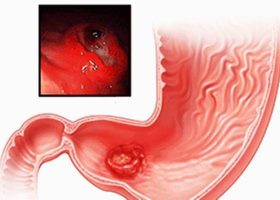

- Аденокарцинома желудка. Она развивается в антральном и пилорическом отделах желудка. Опухоль может проявляться как инфильтрат, язва или полип. Такие образования прогрессируют медленно и могут достигать размеров до 10 см. Иногда бессимптомное течение продолжается несколько лет. Опухоль активно прорастает в соседние ткани и плохо поддается лечению.